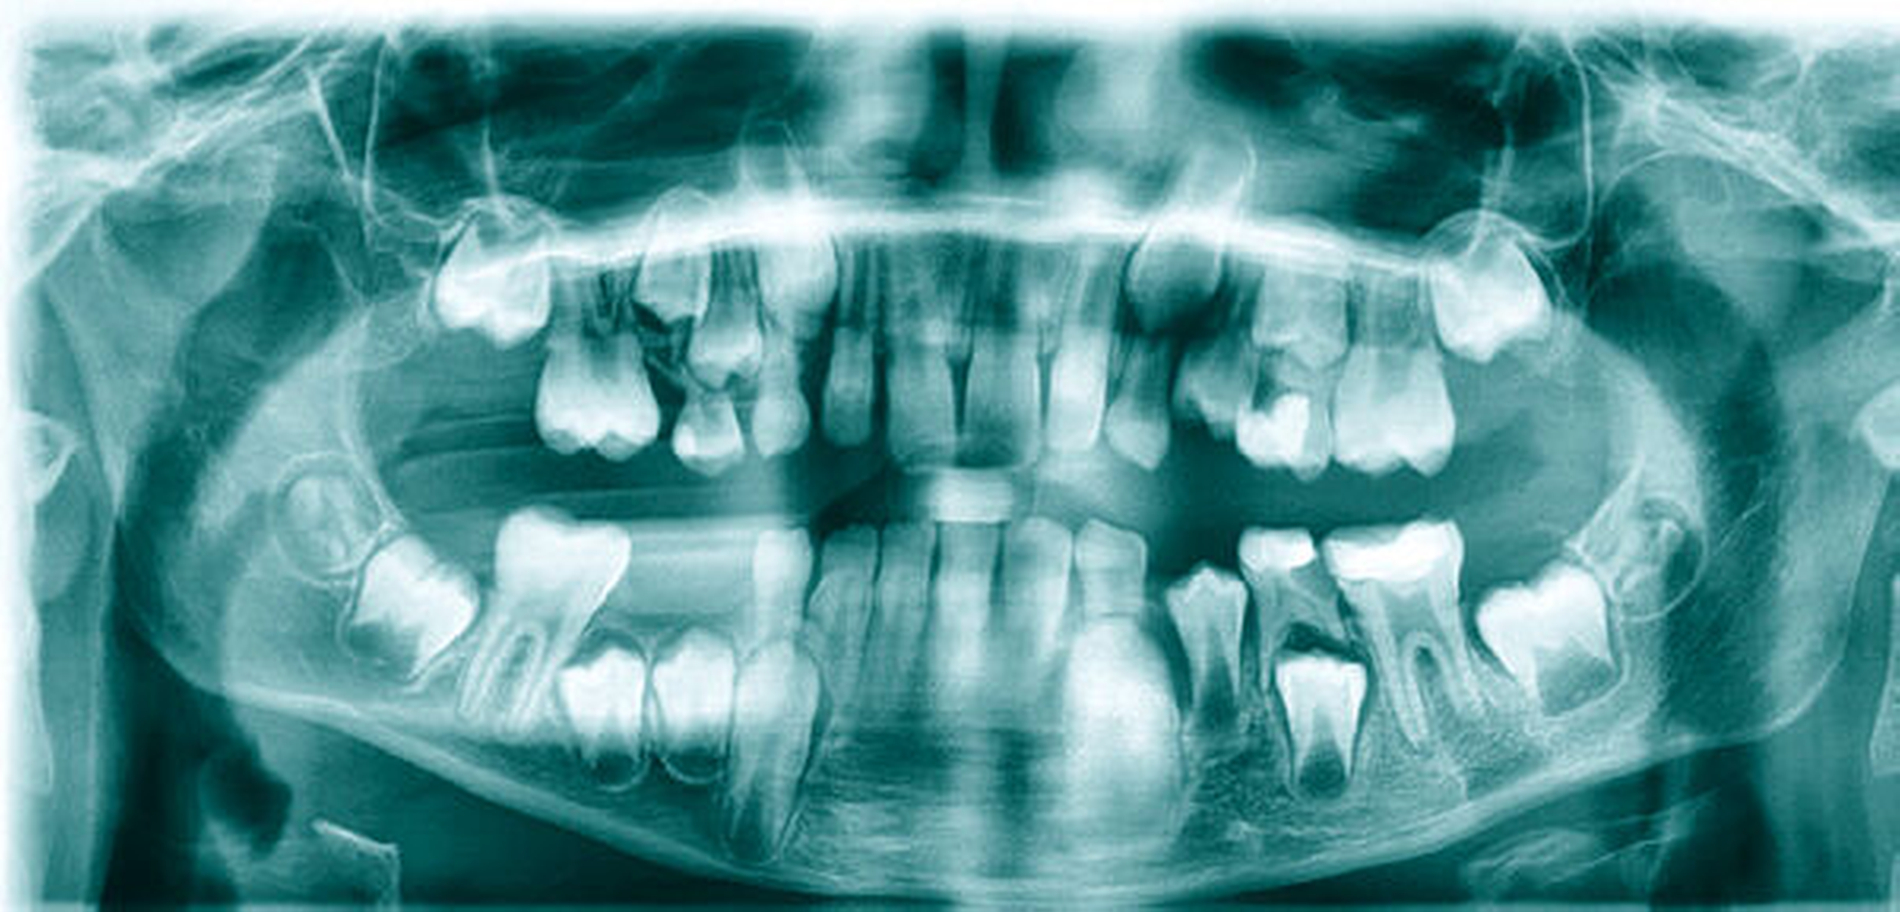

Zum Zeitpunkt der Erstvorstellung in unserer Ambulanz zeigte sich klinisch submandibulär links ein 5 cm langes Narbenkeloid mit zentraler Einziehung (Abbildung 1). Bei Palpation kam es zum Austritt von blutig-eitrigem Sekret. In der Panoramaschichtaufnahme war eine Aufhellung der distalen Krone des Zahnes 75 sowie eine apikale Transluzenz ausgehend von der distalen Wurzel des Zahnes 36 zu erkennen (Abbildung 2). Klinisch waren beide Zähne perkussionsempfindlich bei positiver Sensibilität des kariösen Zahnes 75 und negativer Sensibilität des Zahnes 36.

Bei extraoraler Fistelbildung mit vorrangig dermatologischen Symptomen im Gesicht sollte eine dentogene Ursache immer mitberücksichtigt werden [Sack et al., 1992]. Für die Diagnostik einer extraoralen odontogenen Fistel sind die klinische und die radiologische Untersuchung entscheidend. Bei einer chronisch granulierenden Entzündung nach Partsch imponiert klinisch extraoral häufig ein rötlicher Knoten mit eitrigem Abfluss beim Abtasten. Die ursächlichen Zähne reagieren häufig positiv auf Perkussion und negativ auf Vitalitätstestungen [Chen et al., 2016]. Für die radiologische Untersuchung bieten sich die Panoramaschichtaufnahme und der Zahnfilm an [Buch et al., 2003].